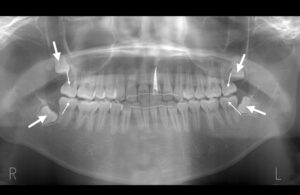

セファロレントゲンで親知らずが存在することが確認できる。親知らずを抜歯したスペースを利用して矯正治療を行いたいが、

22歳時:親知らずを抜歯することができる位置まで萌出してきたので親知らずを抜歯し、そのスペースを利用する。